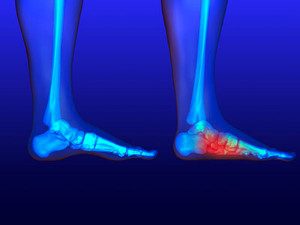

What Foot Problems Can Arise During Pregnancy?

One problem that can occur is overpronation, which occurs when the arch of the foot flattens and tends to roll inward. This can cause pain and discomfort in your heels while you’re walking or even just standing up, trying to support your baby.

Another problem is edema, or swelling in the extremities. This often affects the feet during pregnancy but tends to occur in the later stages.

Pregnancy can create additional pressure on the feet, making certain everyday activities and responsibilities difficult for women. Women who work desk jobs should ensure that they’re sitting in chairs that offer optimal support, while women who spend a majority of their time standing should occasionally elevate their feet using a foot rest. Wearing comfortable shoes is also a must and should never be overlooked. Elevating the feet can also help pregnant women in managing edema, as the feet often swell during pregnancy.

Pregnancy can create additional pressure on the feet, making certain everyday activities and responsibilities difficult for women. Women who work desk jobs should ensure that they’re sitting in chairs that offer optimal support, while women who spend a majority of their time standing should occasionally elevate their feet using a foot rest. Wearing comfortable shoes is also a must and should never be overlooked. Elevating the feet can also help pregnant women in managing edema, as the feet often swell during pregnancy.

Pregnant women with swollen feet can be treated with a variety of different methods that are readily available. For more information about other cures for swollen feet during pregnancy, consult with Brent Harwood, DPM from Southeast Podiatry. Our doctor will attend to all of your foot care needs.